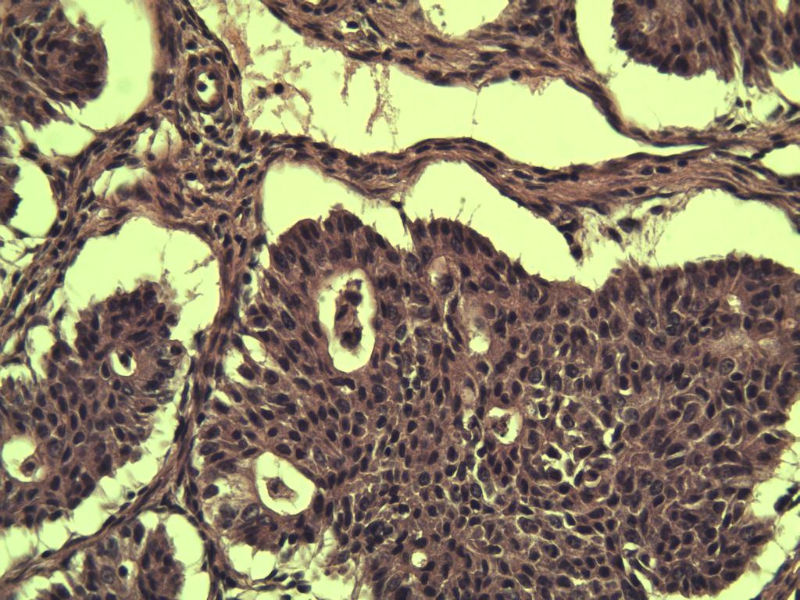

42岁 经期延长 流血量增多 3月余 请各位老师看看 够内膜癌不? 谢谢!